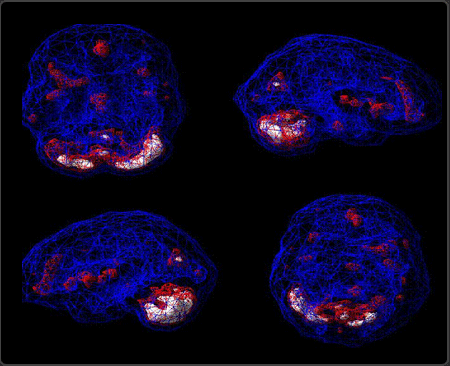

This is a deep brain for a healthy young woman. You still have the four views (Inferior, Right, Left and Superior) but now you can see how different brain systems deep within the brain are operating. Is certain area overactive? Under active? Just right? In this young woman’s case, her brain healthy.

This scan was taken while this young woman was doing a Conner’s Concentration Task. This is healthy scan for women age 22 years of age to 27 years of age. Age and gender make a difference in scan interpretation. The brightest structure in brain is her cerebellum, which is normal.